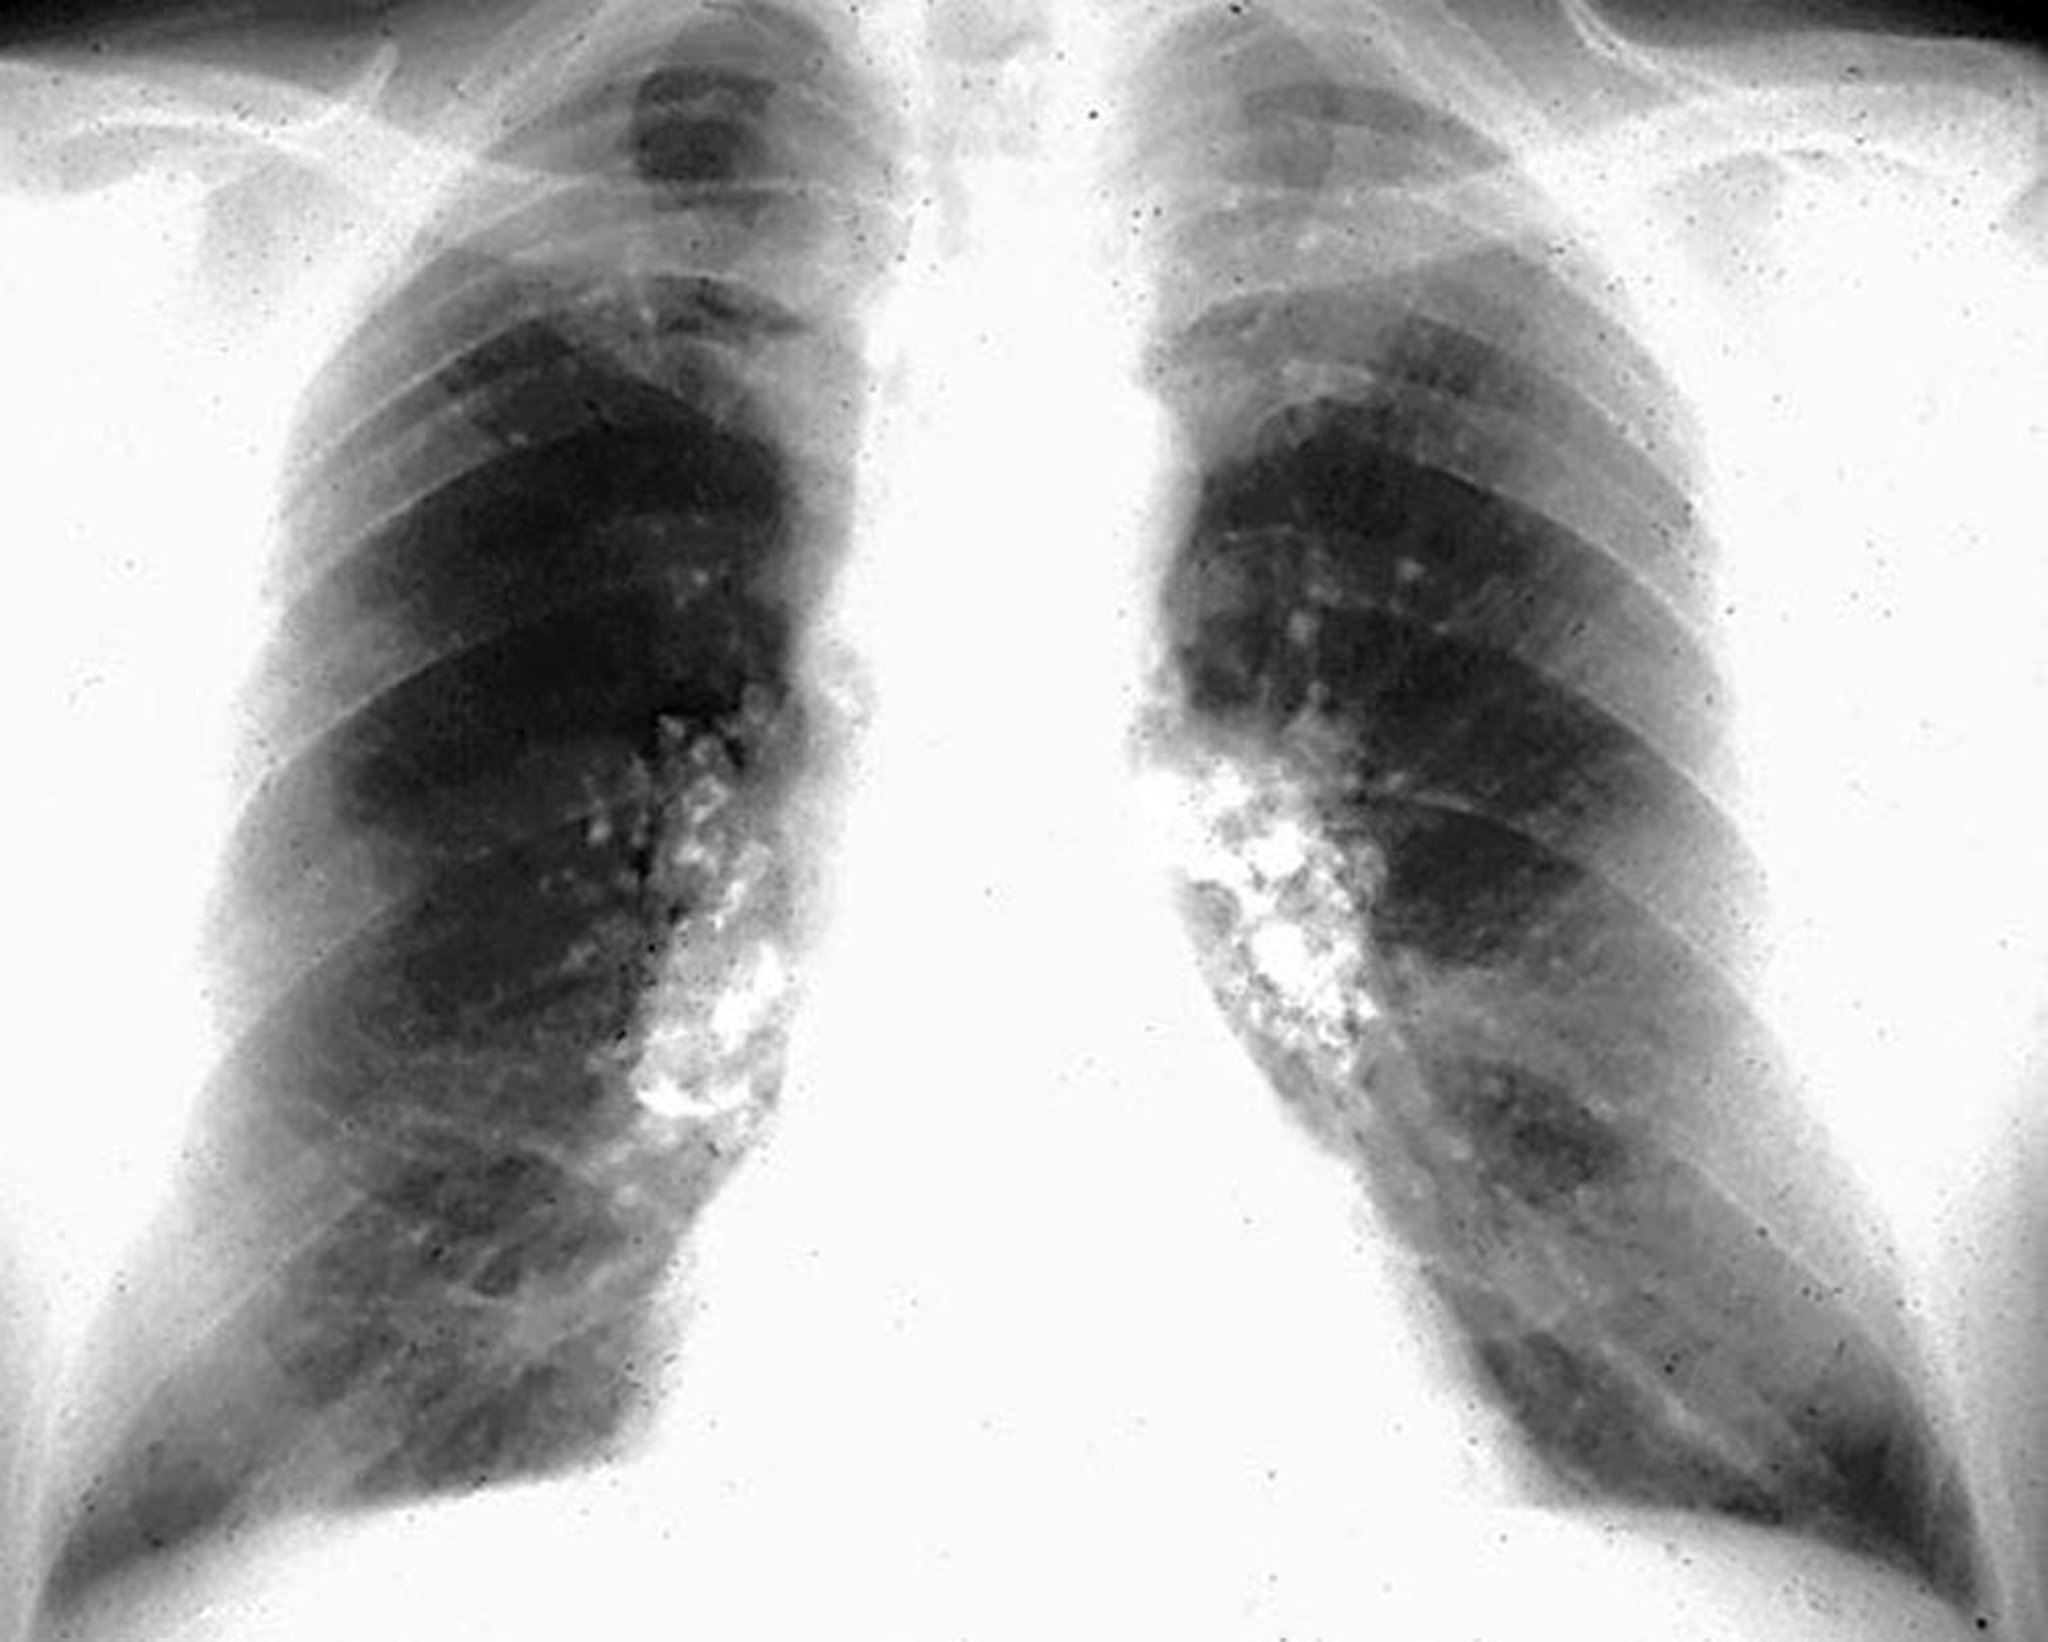

珪肺症—卵殻様石灰化

Image courtesy of David W.Cugell, MD.

珪肺症